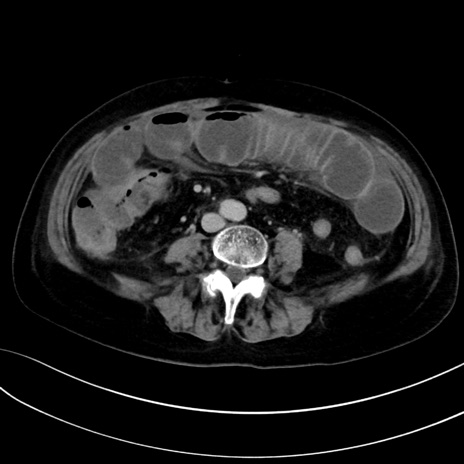

症例13 CT(横断像)1日半後